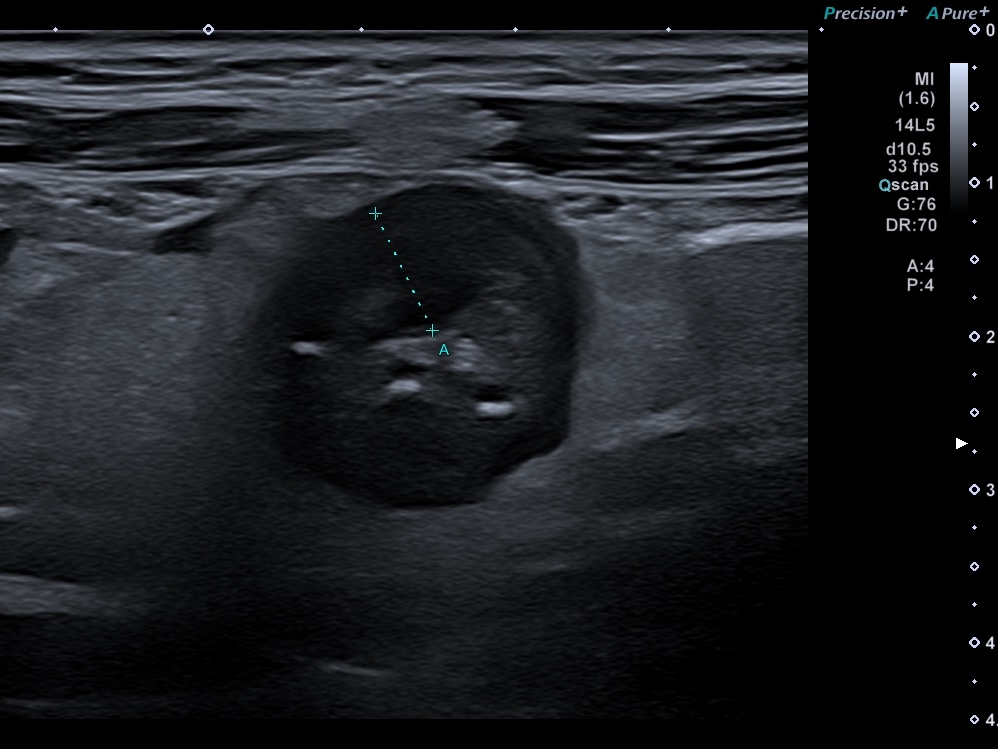

Ganglions inflammatoires (> 6 mm de petit axe)

En cas d'inflammation, on peut voir 4 types de modifications échographique: